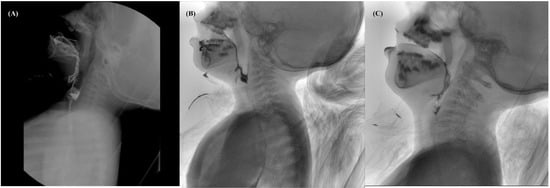

Figure 1. Video Fluoroscopic Swallowing Study (VFSS) of patient 1. (A) VFSS at 15 months using pureed foods (IDDSI level 4). More than half of the food remained as oral residue, and significant aspiration of pyriform sinus residue without a cough reflex (PAS 8) was observed. (B) VFSS at 32 months using pureed foods (IDDSI level 4). Some collections of oral residues were observed, and food penetration was shown with little contrast in the laryngeal vestibule (PAS 5). (C) VFSS at 5 years using pureed foods (IDDSI level 4). The lining amount of the oral residue was observed, the amount of pharyngeal residue was significantly reduced, and no penetration or aspiration was seen (PAS 0).

A 13-month-old boy born at 39 weeks gestation after an uncomplicated pregnancy and cesarean section delivery visited the outpatient clinic for dysphagia and developmental delay. Because of respiratory insufficiency, he was given mechanical ventilation for 3 days after birth. Due to poor sucking reflex, he was fed by nasogastric tube until 7 months of age and then started to eat pureed foods (International Dysphagia Diet Standardization Initiative (IDDSI Level 4)), but it was still difficult to eat. He had clinical features of generalized hypotonia, dysarthria, dysphagia, and facial weakness with an open mouth and drooling. In the Video Fluoroscopic Swallowing Study (VFSS) performed using pureed foods (IDDSI level 4) at 15 months of age, poor lip closure and tongue control without bolus transport were observed, and more than half of the food remained as oral residue. The initiation of pharyngeal swallowing was severely delayed, and minimal laryngeal elevation and epiglottic movement were observed with the aspiration of pyriform sinus residue without a coughing reflex (penetration–aspiration scale, PAS 8) (Figure 1A). We decided to start the dysphagia therapy twice weekly, 30 min per session, while maintaining the diet. Since he avoided oral and facial stimuli and no chewing response was observed when food was given, we massaged the oral structures to facilitate tongue and lip movements and induced a swallowing response by providing passive sensory stimulation. Twice-weekly, 30 min of neuromotor electrical stimulation for each session was used to strengthen the anterior neck muscles. We applied a biphasic symmetric pulsed current with a phase duration of 300 µs an interphase duration of 100 µs, and a pulse duration of 700 µs, resulting in a frequency of 80 Hz. The intensity of the current started from 4.5 mA and was adjusted to 6~7 mA until laryngeal elevation was palpated or observed by the therapist. A pair of electrodes was placed horizontally on the skin just above the hyoid or thyroid notch [8,9]. In addition, parents were educated on oral and facial massage that can be performed at home. At 34 months of age, a muscle biopsy revealed nemaline rod myopathy, and NEB gene mutation was confirmed by genetic examination.

At the follow-up, VFSS was performed using pureed foods (IDDSI level 4) at 2 years (32 months), anterior to posterior bolus transport, and some collections of oral residues were observed. Although the initiation of pharyngeal swallowing was still delayed, the laryngeal elevation and epiglottis movement was improved, and food penetration was shown with little contrast in the laryngeal vestibule (PAS 5). (Figure 1B). At the age of 3 years (44 months), the VFSS was conducted with cheese (IDDSI level 6). Although bolus preparation was prolonged, and some collection of oral residues remained, the initiation of pharyngeal swallowing was significantly improved. Further improvements in laryngeal elevation, epiglottis movement, and laryngeal vestibular closure were observed, with mild penetration in pureed foods (IDDSI level 4, PAS 3) and thin liquid (IDDSI level 0, PAS 2). While chewing, the stability of the neck and jaw was insufficient, and the oral motor muscles were weak. Therefore, we performed Shaker exercise and buccinator and masseter muscle strengthening exercises using resistance during the therapy sessions. In VFSS at 4 and 5 years of age, slices of strawberry (IDDSI level 6) were tried, and bolus preparation and transport efficiency continued to improve. A trace amount of oral residue was observed. The amount of pharyngeal residue was markedly reduced, and no penetration or aspiration was seen in any of the diets evaluated, including pureed foods (IDDSI level 4, PAS 0) and thin liquid (IDDSI level 0, PAS 0) (Figure 1C). He is now 6 years old and can eat uncooked side dishes (IDDSI level 6). As the dysphagia improved, the caregiver reported reduced mealtime and that the patient had become able to eat safely.